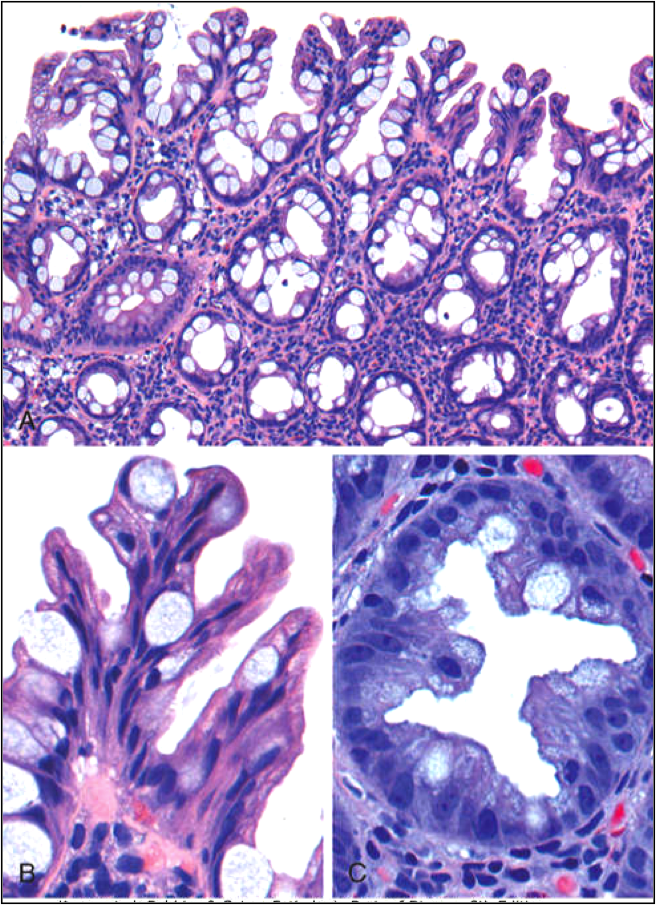

Tubulovillous Adenoma

(Intestinal adenomas can be Tubular, Villous, or Tubulovillous)